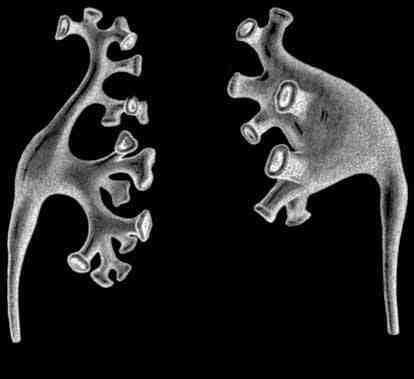

Основной структурной и функциональной единицей почки является нефрон. Нефрон представляет собой почечное тельце и канальцы, длина которых у одного нефрона колеблется между 50 и 55 мм, в то время как длина всех нефронов, расположенных в двух почках, составляет примерно 100 км. В каждой почке имеется более одного миллиона нефронов, которые имеют функциональную связь с кровеносной системой. Начальная часть нефрона — это капсула почечного (мальпигиева) тельца, которая переходит в удлинённый канальце, впадающий в собирательную трубочку.

Структурно нефрон включает почечное тельце, состоящее из капсул (капсулы Шумлянского–Боумена) и клубочка, проксимальную часть канальца, петлю нефрона (петлю Генле) и дистальную часть канальца (см. рис. 5).

Рис 5. Структура и кровоснабжение нефрона (схематически): 1 – капсула клубочка (капсула Шумлянского–Боумена); 2 – клубочек почечного тельца; 3 – просвет капсулы клубочка; 4 – проксимальная часть канальца нефрона; 5 – капилляры; 6 – собирательная трубочка; 7 – петля нефрона; 8 – дистальная часть канальца нефрона; 9 – артерия; 10 – вена; 11 – приносящая клубочковая артериола; 12 – выносящая клубочковая артериола